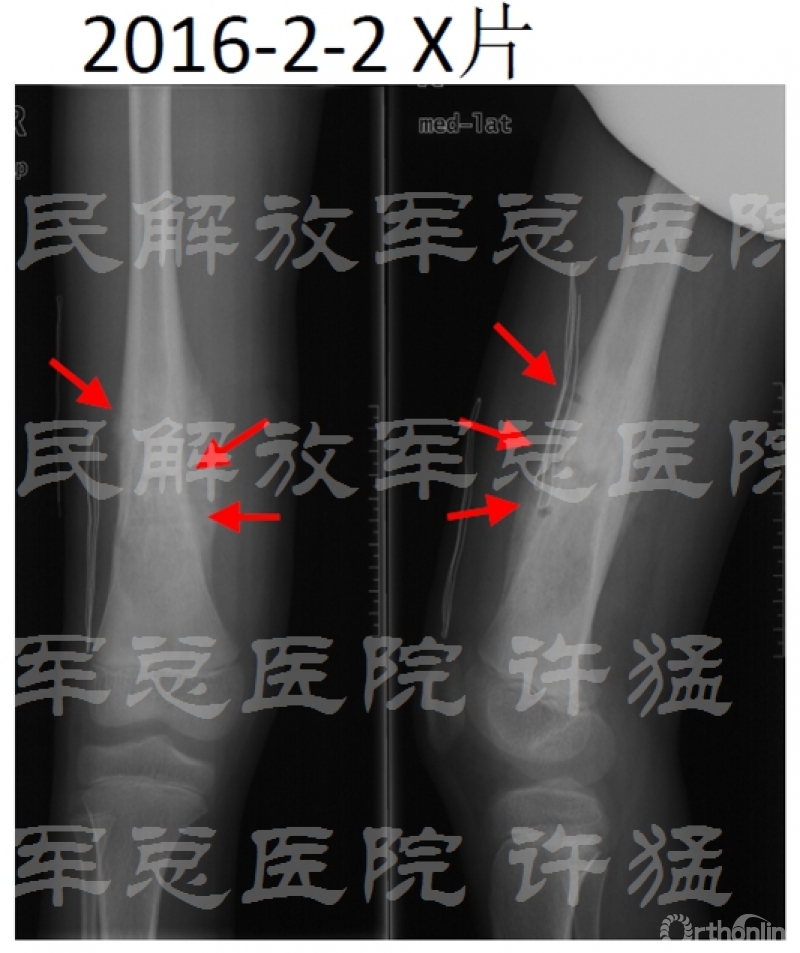

治疗前相关检查:

核磁显示穿刺通道有污染伸膝装置的可能